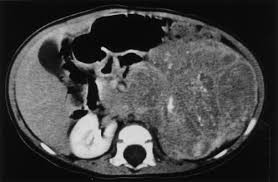

You are seeing a small male for a routine 3-year-old check-up. During the physical exam, you discover a firm, nontender, nonmobile mass in the left upper quadrant of the abdomen.

CBC shows slight lymphocytosis and thrombocytosis. CT scan (shown) shows a large, calcified mass originating from the left adrenal gland. The mass crosses the midline displacing the spleen and left kidney. Chest CT was normal.

What is the most likely diagnosis?

NeuroblastomaWhat additional test can help you make the diagnosis?

24 hr urine catecholamines (VMA, HVA); can also do spot urine catecholamines while awaiting 24hr results. OR Biopsy for diagnosis and staging -